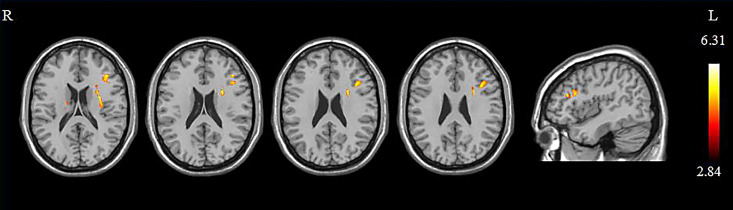

Methods: Twenty-two mild cognitive impairment participants who were randomly assigned to the real and the sham groups received 10 sessions and sham-controlled 10 Hz rTMS over the DLPFC. All patients underwent cognitive assessments and diffusion tensor imaging scans before and after the intervention. Brain regions that showed significant differences in fractional anisotropy (FA) values were selected as the regions of interest to calculate the correlation with cognitive scores.

Results: In the real group, FA values in the left middle frontal gyrus and bilateral parahippocampal gyrus increased and in the right superior frontal gyrus decreased. No significant FA change was detected in the sham group. Furthermore, the FA value of the left middle frontal gyrus was positively correlated with Boston Naming Test (BNT) scores. The change of FA value in the right superior frontal gyrus was positively correlated with the change in the Trail Making Test (TMT-B) score.